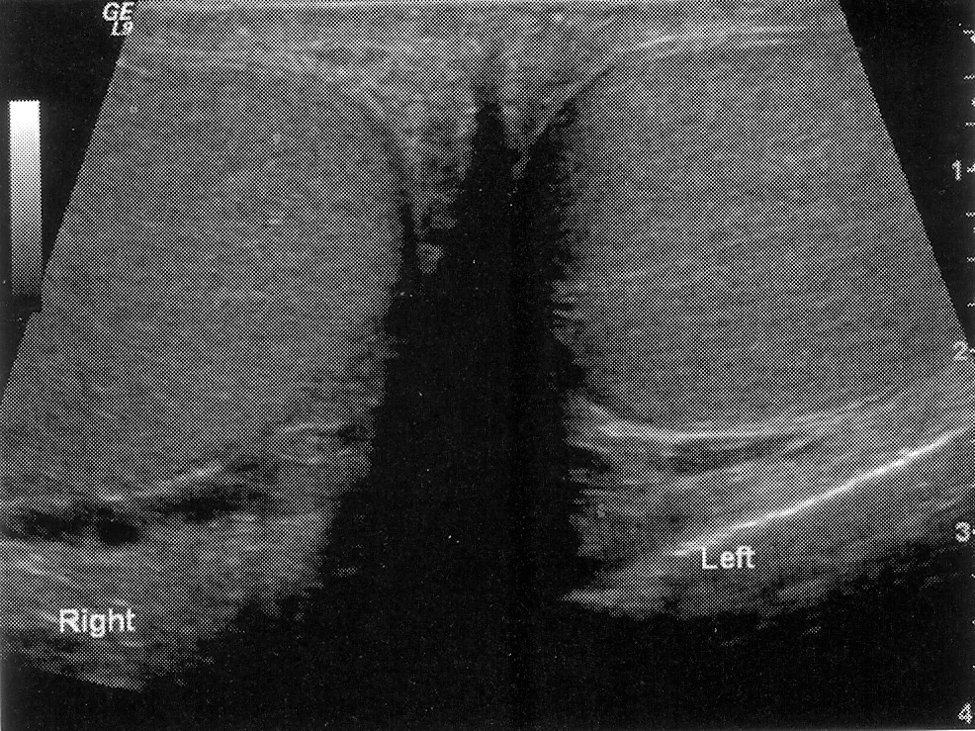

Bicornate Uterus